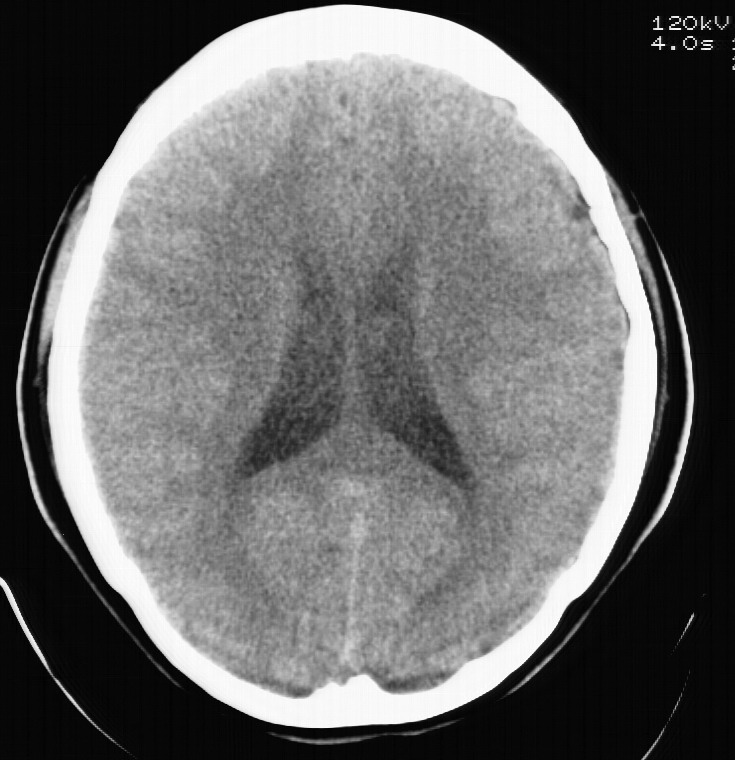

标题: CT5853:右额叶上部占位请会诊

女,34岁,自述头晕胀2年,近期感精神恍惚,无发热,实验室检查阴性。

右顶叶靠近脑表面圆形低密度灶,周围无水肿及占位效应,增强病灶无明显强化,考虑:右顶叶低分级星型细胞瘤。

右额叶上部皮质区见类圆形低密度区,边界不清,无强化,无钙化。

支持大多数战友的意见,1级星形细胞瘤。